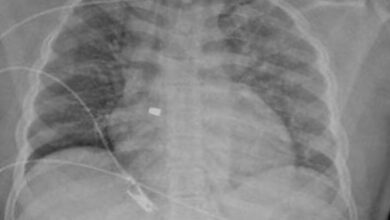

مقيم أصيب بطلقة نارية بالرياض

أحوال – الرياض – زهير الغزال : تمكن فريق مسار الإصابات بتجمع الرياض الصحي الأول من إنقاذ حياة مقيم أصيب بطلقة نارية في منطقة الصدر. وفي التفاصيل، وصل المصاب إلى…